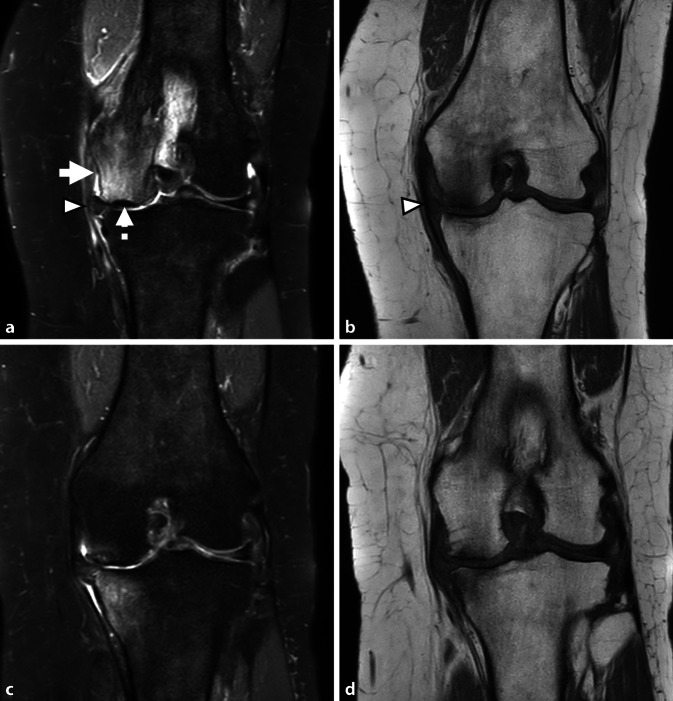

骨髓病变(BML)是在磁共振成像(MRI)上发现的骨髓异常,通常可分为创伤性和非创伤性。本文综述了非创伤性骨髓水肿综合征(BMES)及其影像学评价。MRI仍然是评估BMES的首选方式,特别是使用流体敏感序列,尽管其他序列如Dixon和t1加权成像可以进一步提供帮助。新出现的证据支持双能CT (DECT)作为一种可靠的替代方法,在检测骨髓水肿方面具有高灵敏度和特异性。BMES一词是对短暂性骨质疏松症(TO)和区域性迁移性骨质疏松症(RMO)等病症的统称,主要影响中年个体和孕妇或产后女性的负重骨。膝关节软骨下不全性骨折(SIFK)是BMES的一个关键亚型。这些骨折最常累及股骨内侧髁(MFC),并与危险因素相关,如半月板根撕裂和半月板体挤压。MRI表现通常包括骨髓水肿样信号和软骨下骨折线,并伴有其他特征,如晚期继发性骨坏死。预后指标对患者分层和指导治疗至关重要。低级别或可逆病变通常通过保守治疗解决,而高级别或不可逆病变可能需要手术干预。缺血性坏死是另一种非外伤性BML,不同于BMES,它与全身因素(如类固醇使用或酒精滥用)有关。准确的成像,特别是在早期阶段,对于区分可逆和不可逆病变,促进及时和适当的管理至关重要。

Bone marrow lesions (BML) are abnormalities in the bone marrow identified on magnetic resonance imaging (MRI) and can generally be classified as traumatic or atraumatic. This review focuses on atraumatic bone marrow edema syndromes (BMES) and their imaging evaluation. The MRI remains the modality of choice for assessing BMES, particularly using fluid-sensitive sequences although other sequences such as Dixon and T1-weighted imaging can be of further assistance. Emerging evidence supports dual-energy CT (DECT) as a reliable alternative, with high sensitivity and specificity for detecting bone marrow edema. The term BMES is a collective term for conditions, such as transient osteoporosis (TO) and regional migratory osteoporosis (RMO), predominantly affect weight-bearing bones in middle-aged individuals and pregnant or postpartum females. Subchondral insufficiency fractures of the knee (SIFK) are a key subset of BMES. These fractures most commonly involve the medial femoral condyle (MFC) and are associated with risk factors, such as meniscal root tears and extrusion of the meniscal body. The MRI findings typically include bone marrow edema-like signals and subchondral fracture lines, with additional features, such as secondary osteonecrosis in advanced cases. Prognostic indicators are crucial for stratifying patients and guiding management. Low-grade or reversible lesions often resolve with conservative treatment, whereas high-grade or irreversible lesions may require surgical intervention.Avascular necrosis, another atraumatic BML entity, differs from BMES by its association with systemic factors, such as steroid use or alcohol abuse. Accurate imaging, particularly in the early stages, is vital to distinguish between reversible and irreversible lesions, facilitating timely and appropriate management.